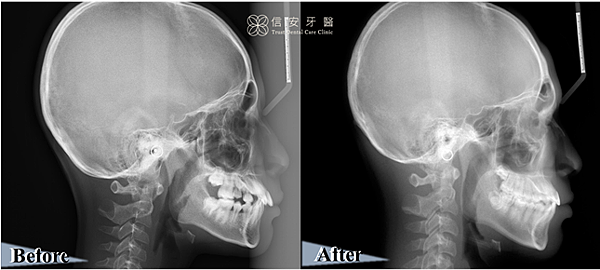

▲從X光可以看到,上顎往內縮、下顎往前生長,原本奔放的齒列已全數列隊排好。